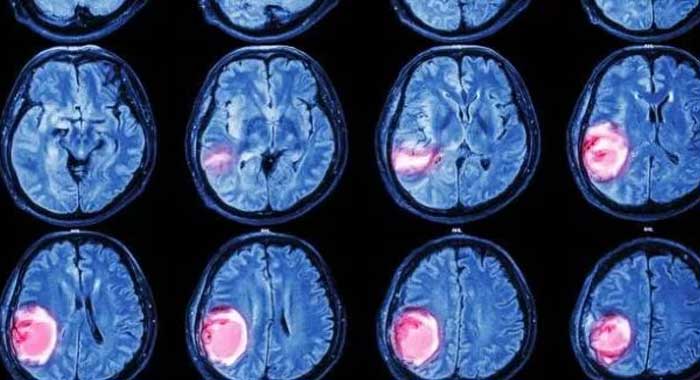

Cerebro : RM muestran tumor cerebral en el lóbulo parietal ... 😈

Resonancia Magnética Del Cerebro El Tumor Cerebral Foto de ... 😈